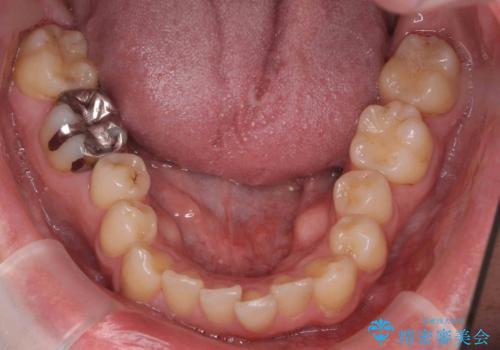

出っ歯と歯のねじれ 非抜歯で 30代男性

- 前歯の並びを気にして来院。

右の歯並びが1本分上が前にずれていました。

奥歯のかみ合わせを特に変えず、前歯の並びを整える治療をおこないました。

今回は右のかみ合わせはそのままにしました。左は特に初めから問題ない状態でした。

右のかみ合わせを変えず部分矯正にしたことによって、治療が短期間で済み、また、ワイヤーでなくインビザラインで治療が可能、歯も抜かなくて済むなどメリットの多い方法であるといえます。